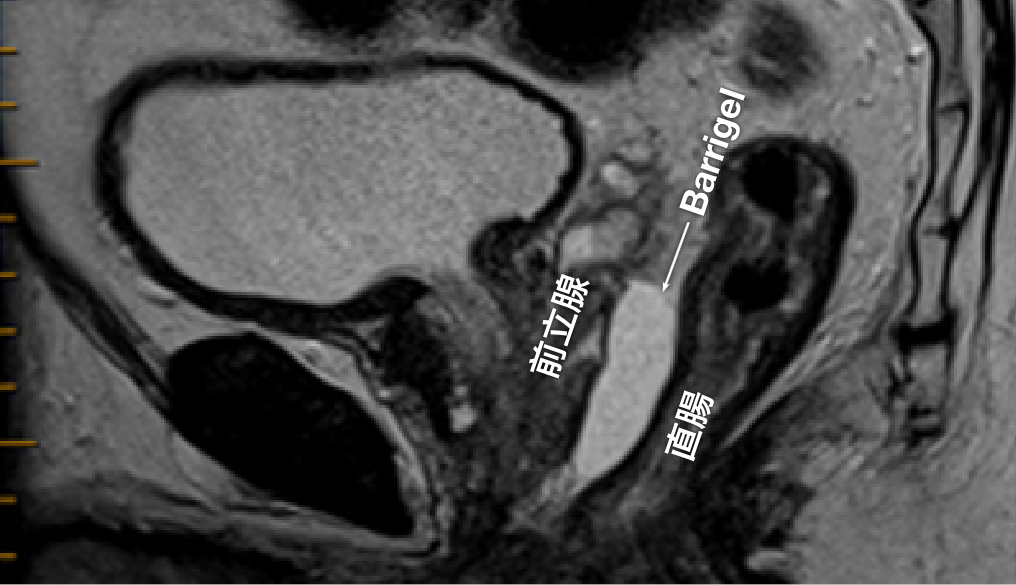

Barrigel留置画像

MRIおよびCTでのBarrigelの留置画像および経直腸超音波(TRUS)でのBarrigelの手技画像をご覧いただけます。

MR 画像

MR画像提供:Prof Michael Chao, MBBS (Hons), FRANZCR, AFRACMA, DMedSc, Radiation Oncologist; Victoria, Australia